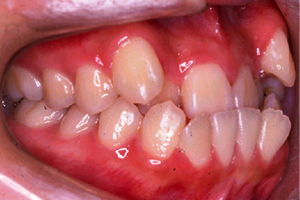

矯正治療前

治療前